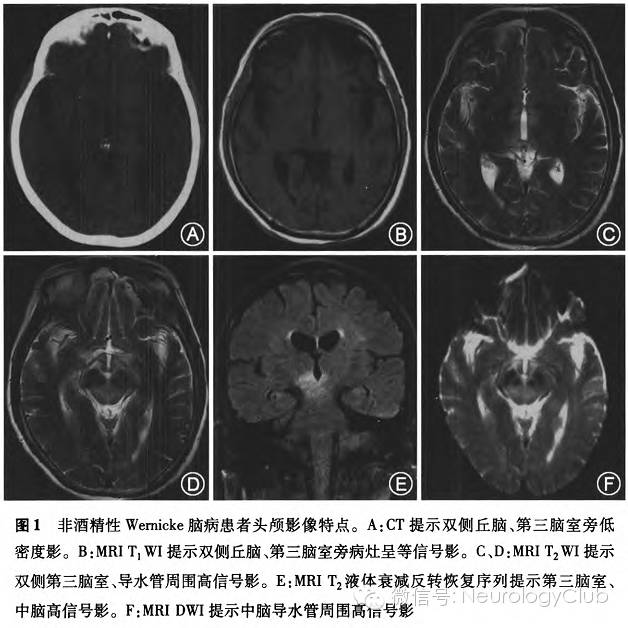

共5例患者行头颅CT检查,16例患者行头颅MRI检查。患者头颅CT和MRI(图1)影像学典型表现为:第三脑室旁、第四脑室旁、中脑导水管周围、乳头体、丘脑异常病灶。在头颅CT表现为低密度影,在MRI表现为T1WI呈等或稍低信号,T2WI上呈高信号,T2FLAIR序列上呈高信号。脑部病灶基本呈双侧对称分布,无占位效应。其中2例患者同时做DWI检查,病灶均表现为DWI高信号,但表观弥散系数(ADC)图提示1例表现为低信号,另1例表现为稍高信号。患者脑部病灶具体分布范围详见表2。

本组病例影像学提示Wernicke脑病表现为双侧丘脑、第三脑室、第四脑室、中脑导水管旁灰质对称性病变,部分病例可累及乳头体、侧脑室旁、尾状核、四叠体及大脑皮质等部位。头颅MRI诊断Wernicke脑病敏感度为53%,特异度为93%。不论病因是酒精性或非酒精性,Wernicke脑病患者的MRI影像学特点都大致相同。酒精中毒所致Wernicke脑病患者影像学上通常伴有乳头体及小脑蚓部的萎缩。酒精中毒可导致小脑损害,故影像学检查可发现小脑萎缩表现;非酒精性Wernicke脑病多数是维生素B1摄入不足所致,小脑萎缩较为罕见。另外,酒精中毒多数是慢性病程,可出现乳头体、小脑蚓部等部位的萎缩;非酒精性Wernicke脑病多数是急性或亚急性起病,短时间内较少出现脑部萎缩表现。我们发现该病磁共振DWI表现为高信号,与国外报道类似;但ADC图有些患者表现为低信号,有些却为稍高信号。其原因可能是病灶早期以细胞毒性水肿为主,故ADC图为低信号;晚期以血管源性水肿为主,故ADC图为高信号。